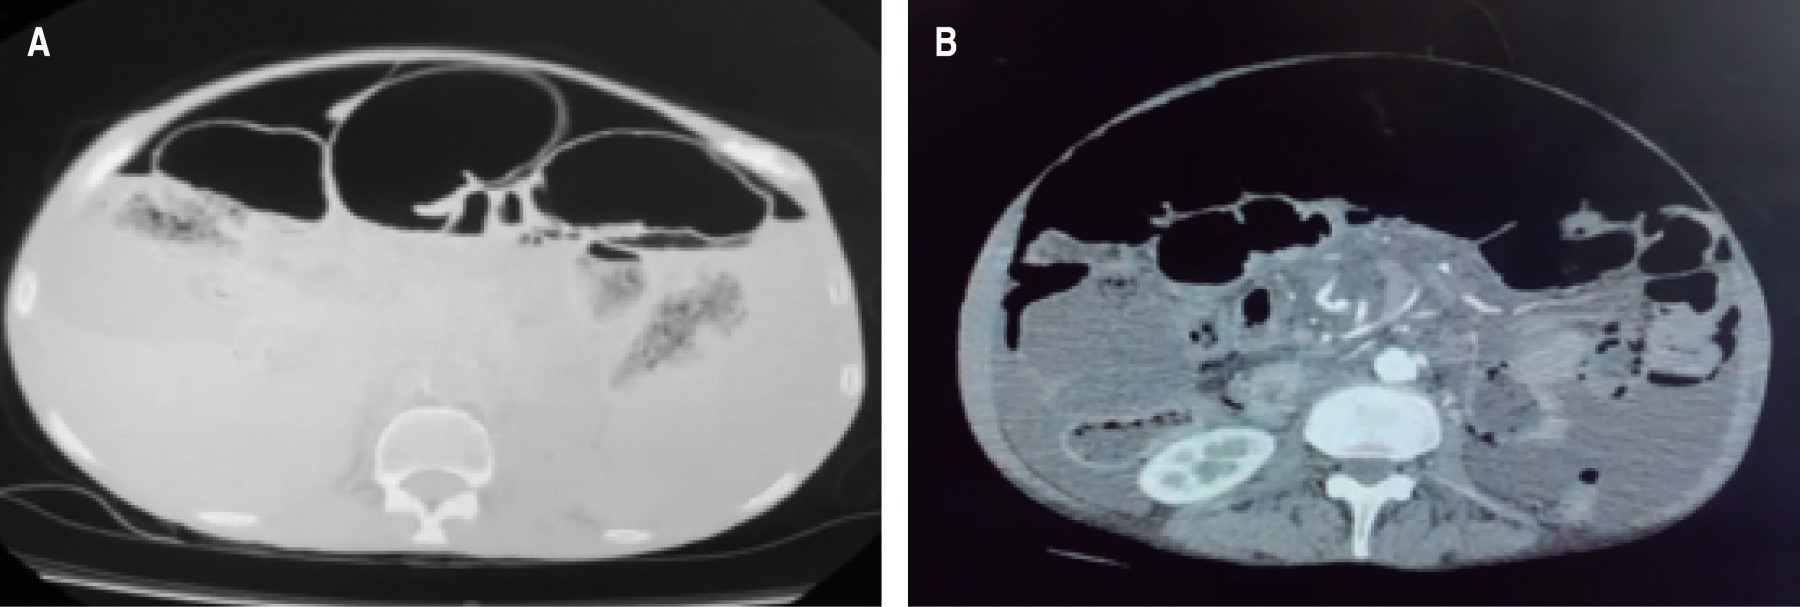

We present the case of a 61-year-old female patient who came to the emergency department with distension, intense and diffuse abdominal pain, intolerance to oral intake, and nausea leading to vomiting with food characteristics of a week's evolution with sudden exacerbation in the last day. As important personal history, she was diagnosed with systemic sclerosis in treatment with immunomodulators, primary hypothyroidism, and chronic liver disease under study, which required therapeutic paracentesis a year ago. The physical examination revealed an afebrile and conscious patient with a globose abdomen tympanic to percussion, decreased peristalsis, pain on deep palpation in the four quadrants, without evidence of peritoneal irritation; no masses or tumors were palpated, there was no ascites fluid under tension, and rectal examination showed no alterations. Laboratory studies were requested on admission without significant alterations, and an ultrasound did not show conclusive changes, with little perihepatic ascites fluid. Conservative management was started with fasting, antibiotic therapy with a double scheme (ciprofloxacin plus metronidazole), and placement of nasogastric tube without exit of food or fecal material through it, without data of improvement, with diaphoresis and progression of abdominal pain, so it was decided to perform a contrasted computerized tomography scan of the abdomen, where air and free liquid in the cavity with high suspicion of intestinal perforation was visualized (Figures 1 and 2). The surgical findings were free air in the abdominal cavity with cystic intestinal pneumatosis of benign origin in the entire small intestine, scarce ascites fluid, and no associated intestinal perforation data (Figure 3). Given this situation, the diagnosis of intestinal pneumatosis was proposed. The evolution was favorable after the three-day intervention with analgesic treatment, antibiotic therapy, and intestinal rest. After six days of remission of the clinical picture, without complications, the patient was discharged and sent to the general surgery outpatient clinic for continued monitoring.

Figure 1

Figure 2